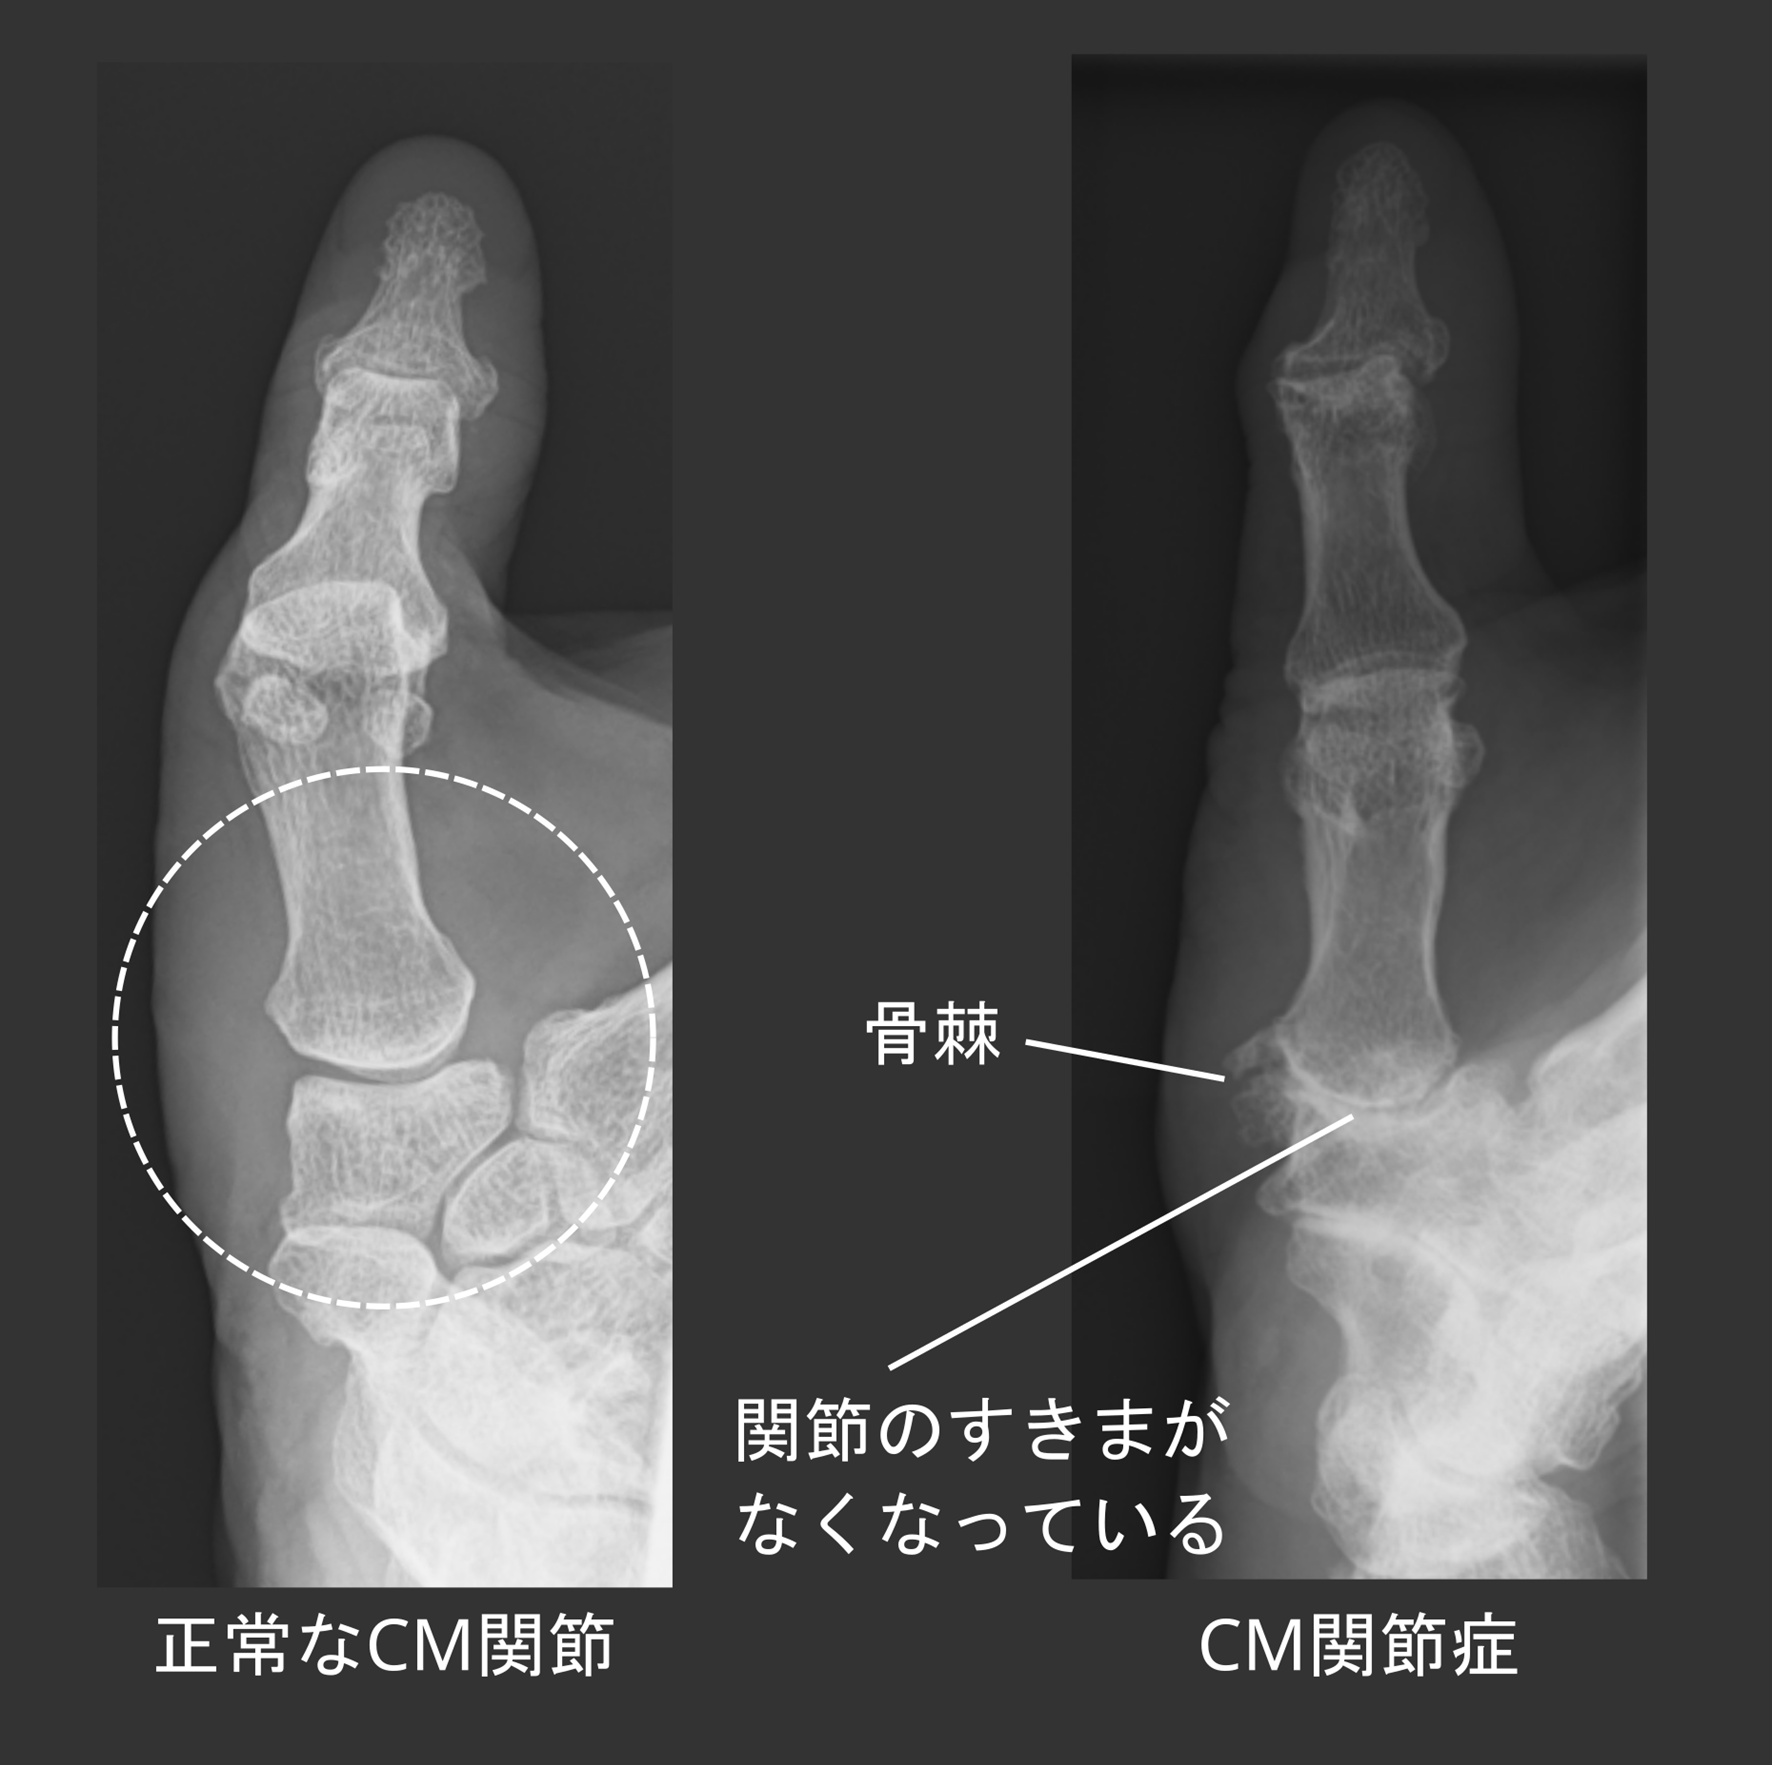

商品説明

「手・肘の外科 診断と治療のすべて」岩崎 倫政定価: ¥ 1600017600円税込#岩崎倫政 #岩崎_倫政 #本 #自然/医療・薬学・健康きれな状態ですが、表紙一部白くなっています。